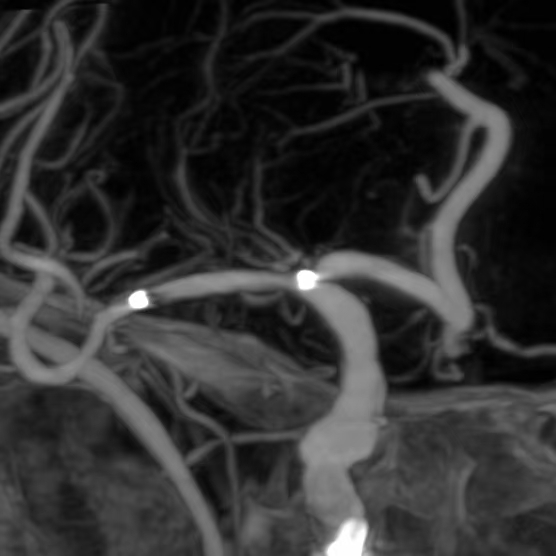

3、第三个患者:我们给予一期外科干预后,一个月后TTP检查发现,狭窄的部位和术后即刻相比是变差的,但与第一次术前相比好转。继续药物治疗狭窄部位存在进行性闭塞的风险。于是二期安全的植入支架,血流完全恢复正常,顺利出院。

一期干预后,一个月复查所见狭窄区为长节段、多发部位狭窄,与术后即刻相比变差了

继续药物治疗存在狭窄部位闭塞的风险,果断给予支架植入

支架植入后,重建后血管的形态,血流完全恢复,顺利出院